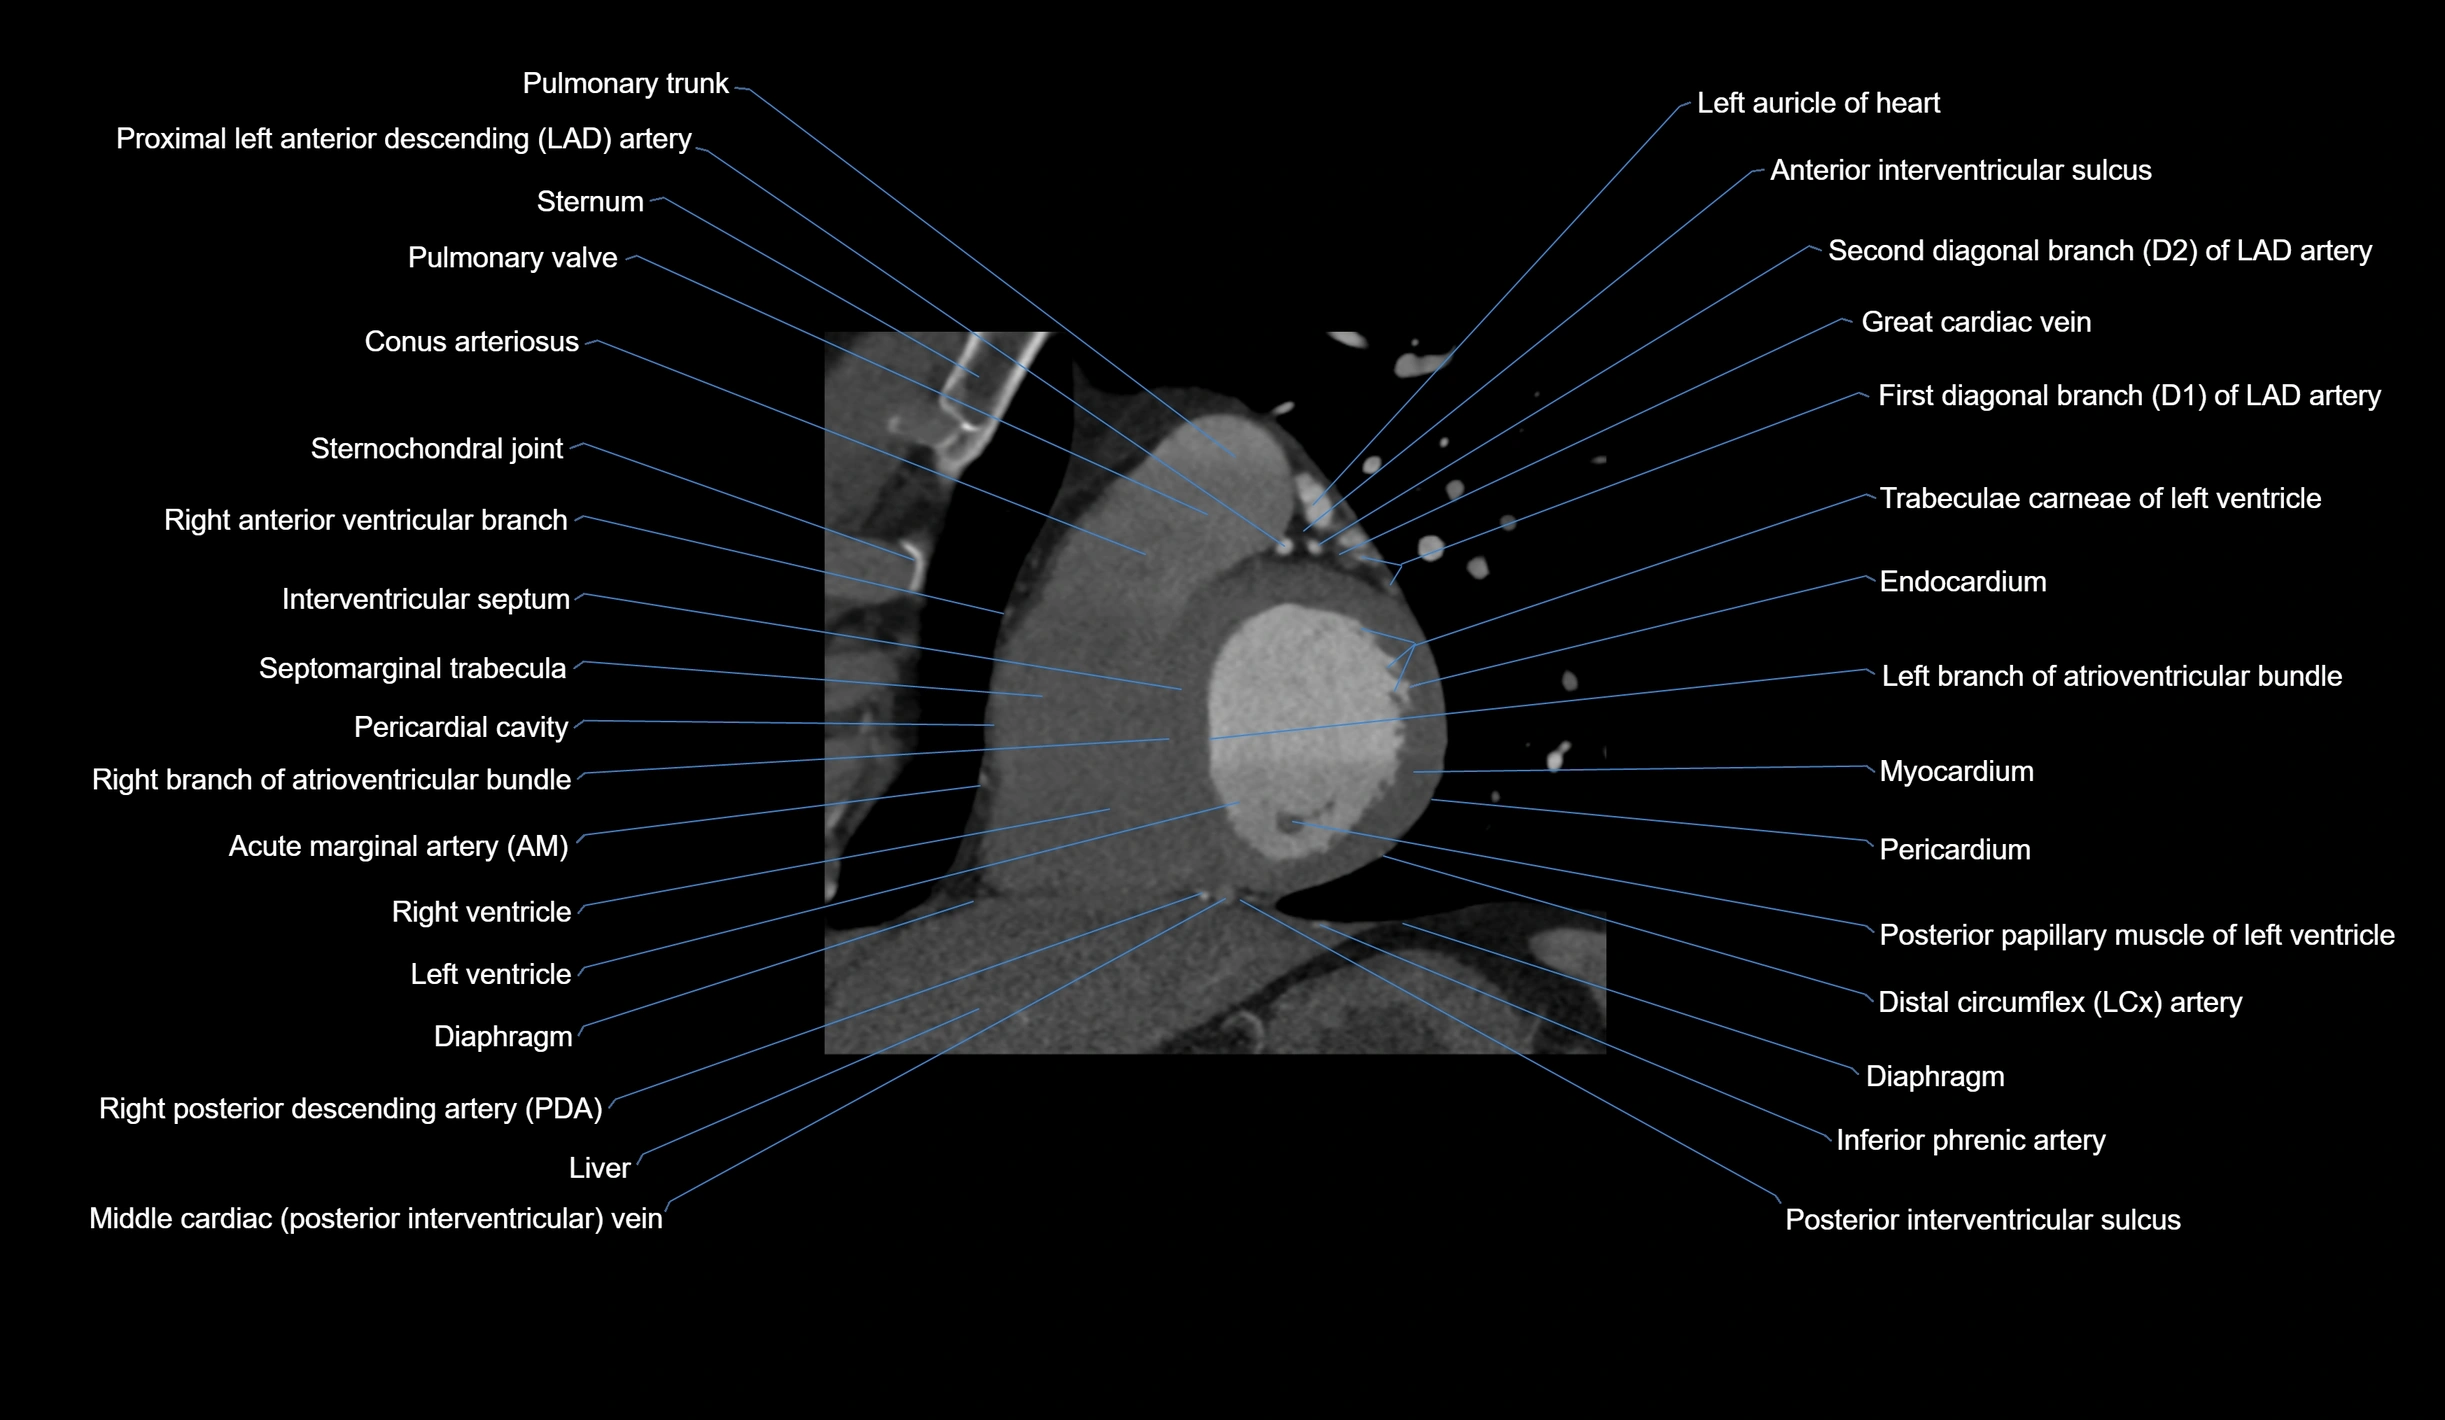

CT images